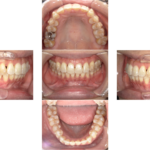

2か月が経過時点での歯列の比較

わたしのマウスピース矯正ははじまったばかりです。